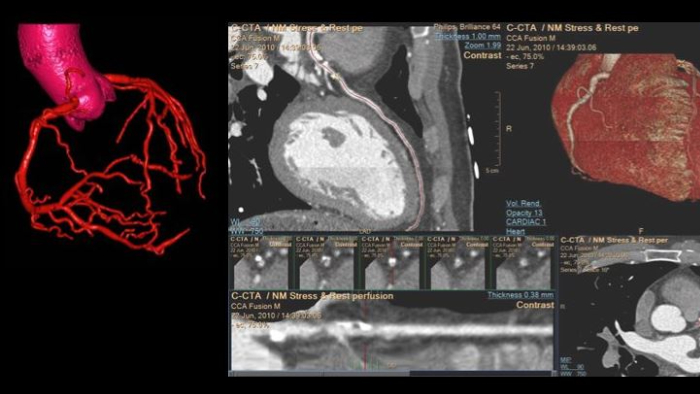

Advanced Visualization Workspace

Review, analyze and quantify clinical information from different modalities and for various clinical indications with AI-enabled 3D models, maps and other quantitative tools.

Spectral CT 7500

Unlock the full potential of a Philips CT as a non-invasive cardiac diagnostic tool.